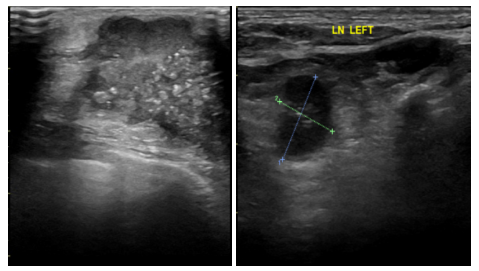

2021-7-29乳腺B超提示:左侧乳腺1-2点钟A环内见大小约21*22*8mm低回声区,边界不清,内见散在强光点,周边可见血流信号。余双侧乳腺腺体形态、结构未见异常。

左侧腋窝见多枚低回声结节,边界清,形态饱满,有包膜,较大者约16*7mm,内可见血流信号。右侧腋窝见多发低回声结节,边界清,有包膜,较大者约10*4mm,血流信号不明显。

影像诊断:左侧乳腺低回声区(BI-RADS:6类);左侧腋窝淋巴结偏大。

图3.乳腺B超(2021-7-29)